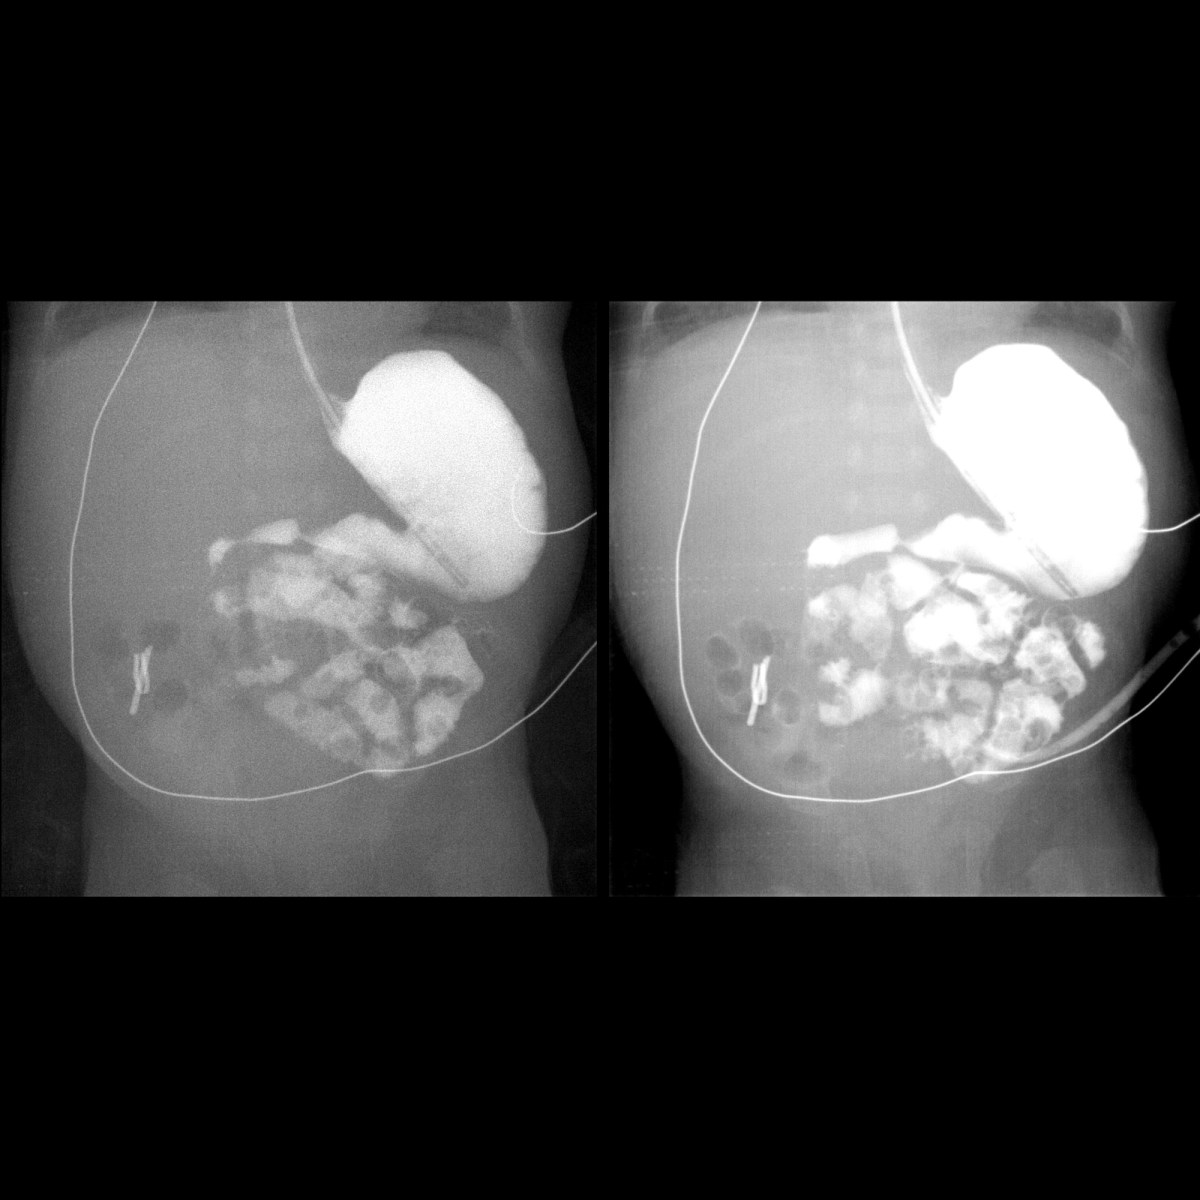

Infant status post surgery for bowel perforation Pediatric Radiology Status Post Vs Post Op imaging assessment of the postoperative spine requires knowledge of. status post (s/p) is a term used in medicine to refer to a treatment (often a surgical procedure), diagnosis or. postoperative fluid collection in the operative bed may represent seroma, csf collection, haematoma, or abscess. abbreviations like “s/p,” denoting “status post,” serve as invaluable shorthand in medical. Status Post Vs Post Op.